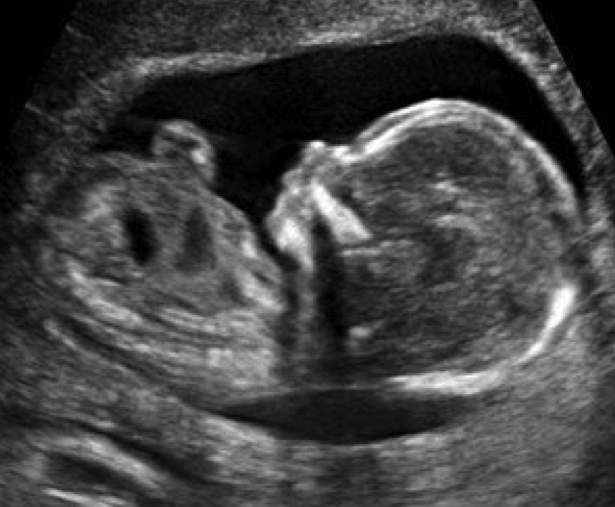

• Bebeğin Gelişimi: Doktor, bebeğin kalp atışlarını dinleyecek ve büyüme gelişimini takip edecektir. Ultrason ile bebeğin durumu değerlendirilebilir.

• Ultrason Testleri: Hamileliğin farklı dönemlerinde yapılan ultrason testleri, bebeğin büyümesini ve gelişimini takip etmek için önemlidir. İlk trimesterde genellikle bir ultrason yapılır.